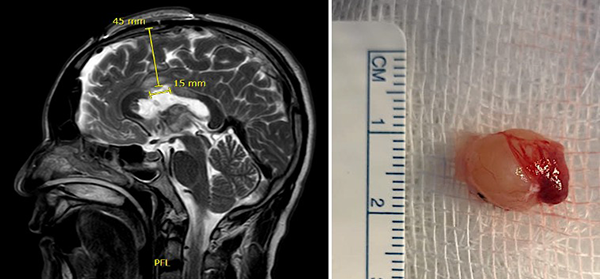

Paciente masculino de 40 años, sin antecedentes patológicos, atendido en nuestra institución por presentar cuadro de 2 años de evolución caracterizado por cefalea holocraneana de moderada intensidad, intermitente. Dos meses previo a la consulta inicial había presentado pérdida de consciencia más un episodio de crisis convulsiva tónico-clónico generalizada. Al examen físico el paciente no presentaba deterioro del sensorio ni déficit neurológico evidente. El resto del examen no mostraba hallazgos relevantes. La resonancia magnética (IRM) evidenció una lesión ovoidea que ocupaba el foramen de Monro, isointensa respecto al parénquima cerebral en las secuencias T1 y T2, de 12x9x9 mm, su margen rostral y dorsal en contacto con el pilar anterior y cuerpo del fornix, respectivamente; con tenue realce a la administración del contraste. En la secuencia de tensor de difusión los diferentes tractos se aprecian con trayecto normal y adecuada disposición de las fibras. Sistema ventricular sin dilatación ni compresiones. Se realizó la exéresis total de la lesión a través de un abordaje interhemisférico transcalloso anterior guiado por sistema de neuronavegación (Figura 1). El curso postoperatorio transcurrió con una hemiparesia braquio-crural derecha transitoria, que cede en días subsecuentes con recuperación total de la fuerza muscular. El paciente fue dado de alta sin déficit neurológico agregado. El examen patológico reportó un quiste coloide. La IRM postoperatoria confirmó la extirpación total de la lesión con cambios postquirúrgicos asociados a craneotomía fronto-parietal derecha (Figura 2). El paciente se encuentra asintomático en seguimiento por la consulta externa.

Figura 2. (A) IRM T2W sagital postoperatoria muestra la ruta de aproximación y longitud de la callosotomía; (B) Imagen de pieza quirúrgica mostrando su exéresis total.